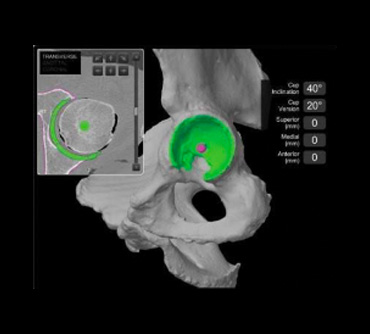

Robotic assisted hip replacement

Jon Conroy Orthopaedics uses state-of-the-art robotic assistance aids to ensure consistent and accurate positioning of implants.This accurate placement is predicted to give optimal performance of your new joint replacement. Our aim is to give you the best functional outcome and longevity for your hip or knee replacement.

The state-of-the-art Mako™ robotic arm system works alongside the surgeon from the pre-surgery planning stage through to assisting in the surgery itself in order to improve the accuracy and precision of the procedure.

Learn more on our ‘Robotic-assisted surgery’ page.